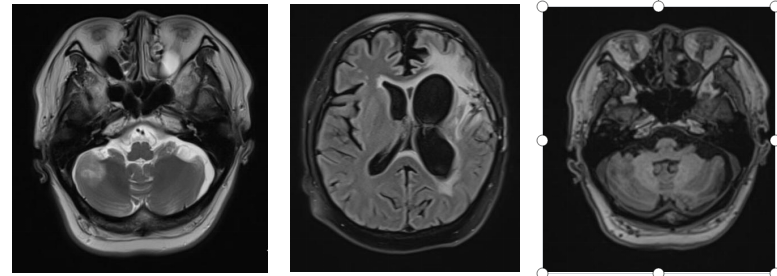

Figure 6: The prescribed dose for the left frontotemporal lobe mass is 45 Gy (RBE) in 15 fractions.

Figure 7: Treatment plan: Prescription dose: The PTVm prescription dose is 60 Gy (RBE) in 20 fractions.